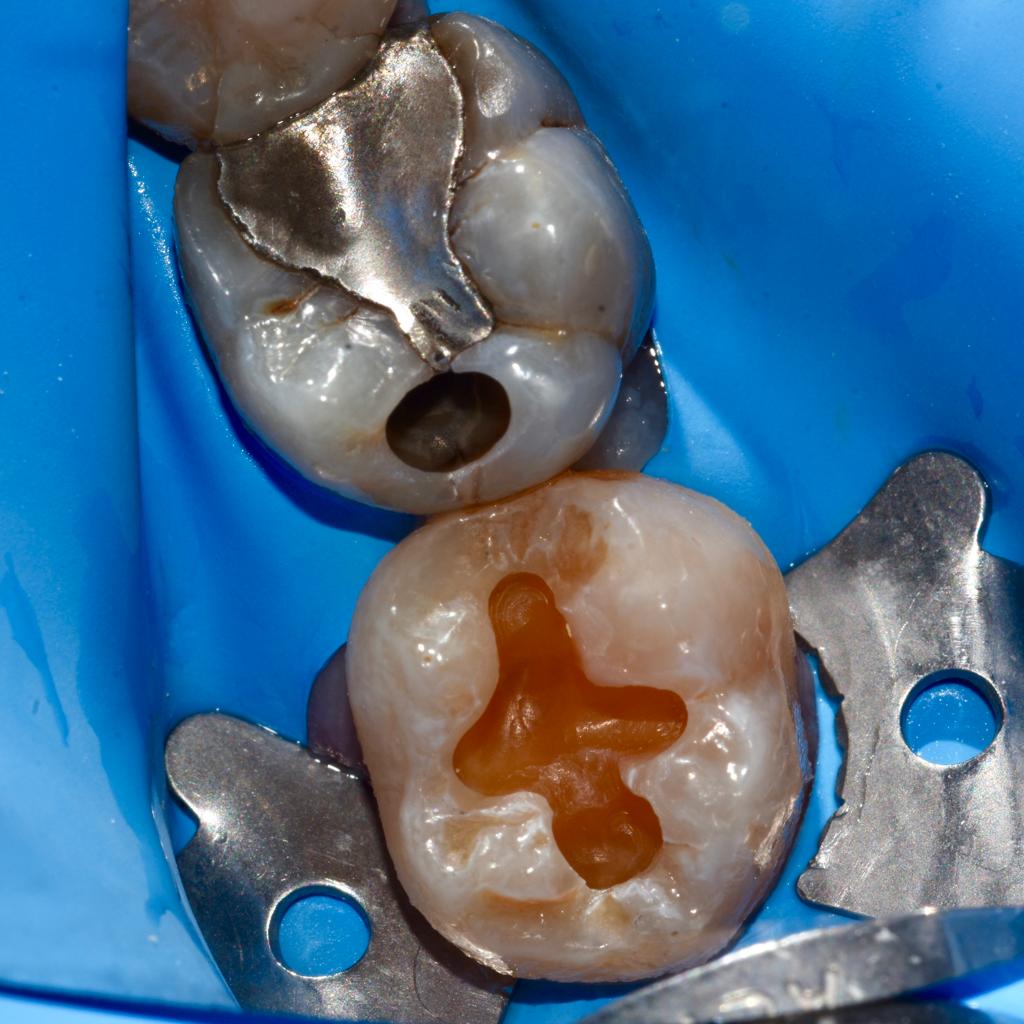

Attraverso l’utilizzo di uno strumentario adeguato, la moderna conservativa si basa sul concetto di minima invasività. Cioè la rimozione esclusiva del tessuto dentario danneggiato dalla carie e la sua sostituzione con materiali da otturazione.

Lo studio Kennedy si avvale di materiali di alta qualità oltre che di specifici protocolli clinici per restituire l’integrità del dente trattato oltre che ad una elevata estetica.

Alcuni casi clinici